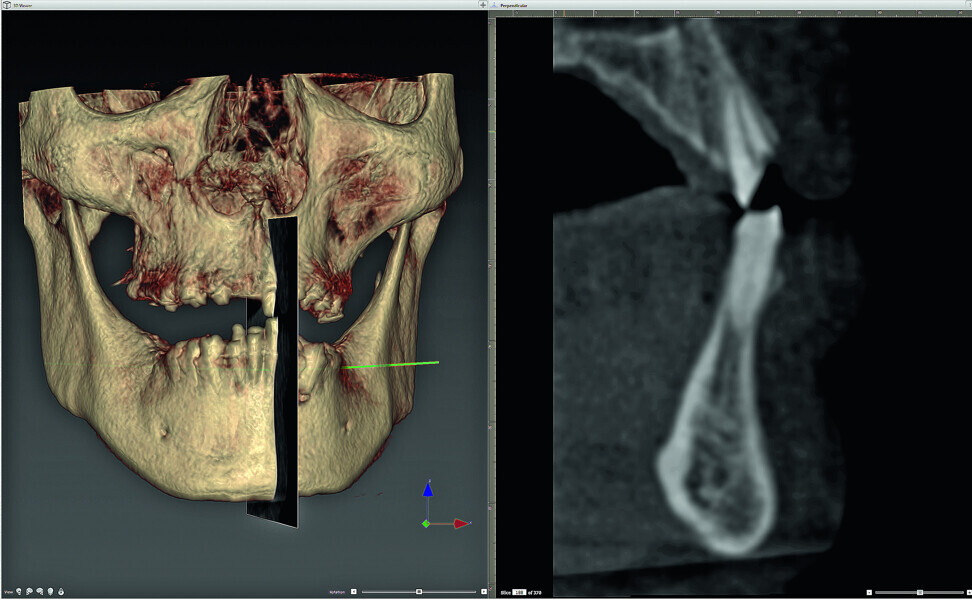

Fig. 1: Three-dimensional volumetric rendering of the maxilla-mandibular relationship (r), and a sagittal section (l) of this region of interest.